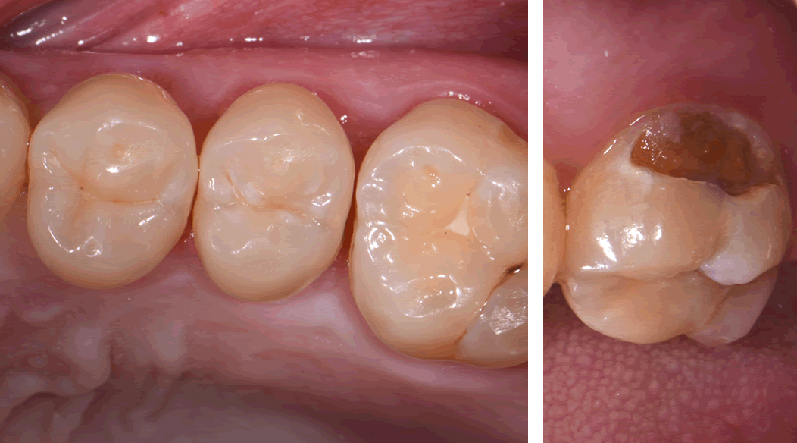

Visual examination revealed decay on the mesial marginal ridge and distal marginal ridge of tooth #13 as well as extensive buccal and occlusal decay on tooth #15 (Figs. 1-2). Bitewing radiographs and intraoral photographs were taken, which confirmed the above diagnosis and also exposed additional decay on the distal of tooth #12 (Figs. 3-4).

Figs. 1 and 2